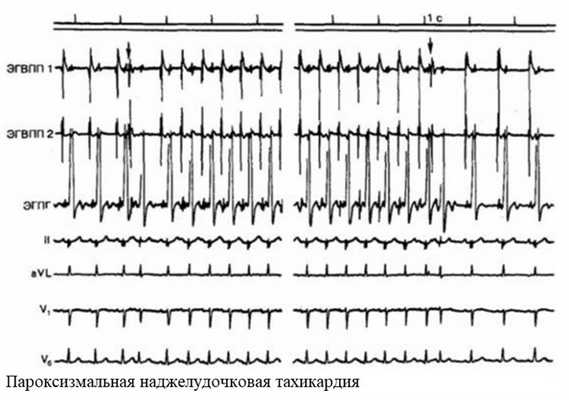

Пароксизмальная тахикардия

Пароксизмальные состояния редко возникают во время беременности без предшествующего фона. Обычно они осложняют ишемию миокарда. По локализации могут быть предсердными и желудочковыми.

Приступ пароксизмальной тахикардии возникает внезапно. Учащается сердцебиение до 200 уд./мин. Могут быть жалобы на шум в ушах, головокружение. У беременных приступ часто протекает на фоне тошноты. Возможно обратимое нарушение речи.

Длительный приступ пароксизмальной тахикардии опасен для матери и плода. Не исключено прерывание беременности.

За три дня до госпитализации женщина почувствовала резкое сердцебиение. Обратилась к участковому гинекологу. Врач направил пациентку на ЭКГ, где была зафиксирована наджелудочковая тахикардия. Женщина была госпитализирована, осмотрена кардиологом и дежурным гинекологом. На момент осмотра осложнений беременности не было выявлено.

При поступлении в стационар на ЭКГ у пациентки регистрировались признаки наджелудочковой тахикардии с ЧСС 200 уд./мин. Проводилась консервативная терапия: Верапамил, калиево-магниевая смесь. Проведено дообследование, на эхоКГ патологии сердца не выявлено. В течение суток состояние пациентки улучшилось, приступ удалось снять. При контрольном КТГ отмечались признаки гипоксии плода (7 баллов по Фишеру). Далее женщина оставалась под наблюдением кардиолога и гинеколога.

Суправентрикулярная пароксизмальная тахикардия (СВПТ) определяется как внезапно возникающая и прекращающаяся с частотой сердечных сокращений более 120 в минуту [2]. Наиболее часто ее источником служит атриовентрикулярный узел (АВ-узловая реципрокная пароксизмальная тахикардия). Морфологической основой СВПТ могут быть и синдромы предвозбуждения миокарда (синдром Вольфа–Паркинсона–Уайта – WPW [Wolff-Parkinson-White] и Клерк–Леви–Кристеско – CLC [Clerc-Levy-Cristesco]). В такой ситуации СВПТ отмечается в 1,2 случая на 1 тыс. населения. У половины пациентов возникновение СВПТ сопровождается определенными жалобами и объективными симптомами (сердцебиение, одышка, гипотония, головокружение, синкопальные состояния) [3].